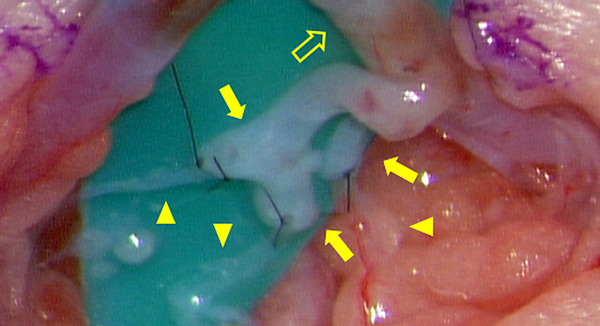

Fig. 3 Open direct lymphangiography (Intraoperative finding) (Case #2)

Lymph node puncture under microscopic dissection, 30 days old, 800 g. Arrow head: Lymph node, Arrow: 27-G needle, Interrupted circle: skin dissected area.

During LG, a contrast agent is injected directly into the lymphatic system; this is also known as direct LG. In adults, a direct puncture is conventionally made in the lymph ducts on the top of the foot.12, 13) This method is difficult to conduct in children, but direct puncture of the inguinal lymph nodes makes it possible to evaluate central lymphatic flow as well (Fig. 3). However, the procedure requires experience and is performed under general anesthesia with positive pressure ventilation in children; therefore, visualization of the main lymph ducts in the thoracic cavity may sometimes be poor.14) Recently, evaluation with dynamic magnetic resonance LG has allowed a more detailed understanding of the pathology.15–17) Leakage sites and patterns have been reported in patients diagnosed as having congenital chylothorax, demonstrating its high diagnostic value.18)